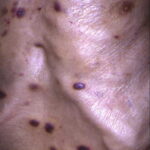

The typical patient with classic KS is a Caucasian male in his sixties with a Mediterranean or Jewish background. The tumors usually start on the skin of the distal portions of the lower extremities as unilateral or bilateral bluish-red (hematoma-like) macules. These lesions tend to progress slowly both horizontally and vertically and develop into firm plaques (Fig. 128-1) and, eventually, into nodules. During tumor progression the color changes to brownish and the skin overlying the tumor becomes hyperkeratotic and, in particular on the lower extremities, may ulcerate. Surrounding the tumor there is frequently a pitting edema which may evolve into fibrosis. Classic KS usually runs a rather benign course slowly extending proximally and patients may sometimes live with slowly progressive disease for decades.38,39,41 After several years of progression (Fig. 128-2), dissemination to other body sites is frequently seen, and tumors may become manifest in lymph nodes, on mucous membranes, and in internal organs such as the gastrointestinal tract where it is rarely symptomatic.41,38 Because classic KS affects mostly elderly patients, death from other causes may precede its full spread.